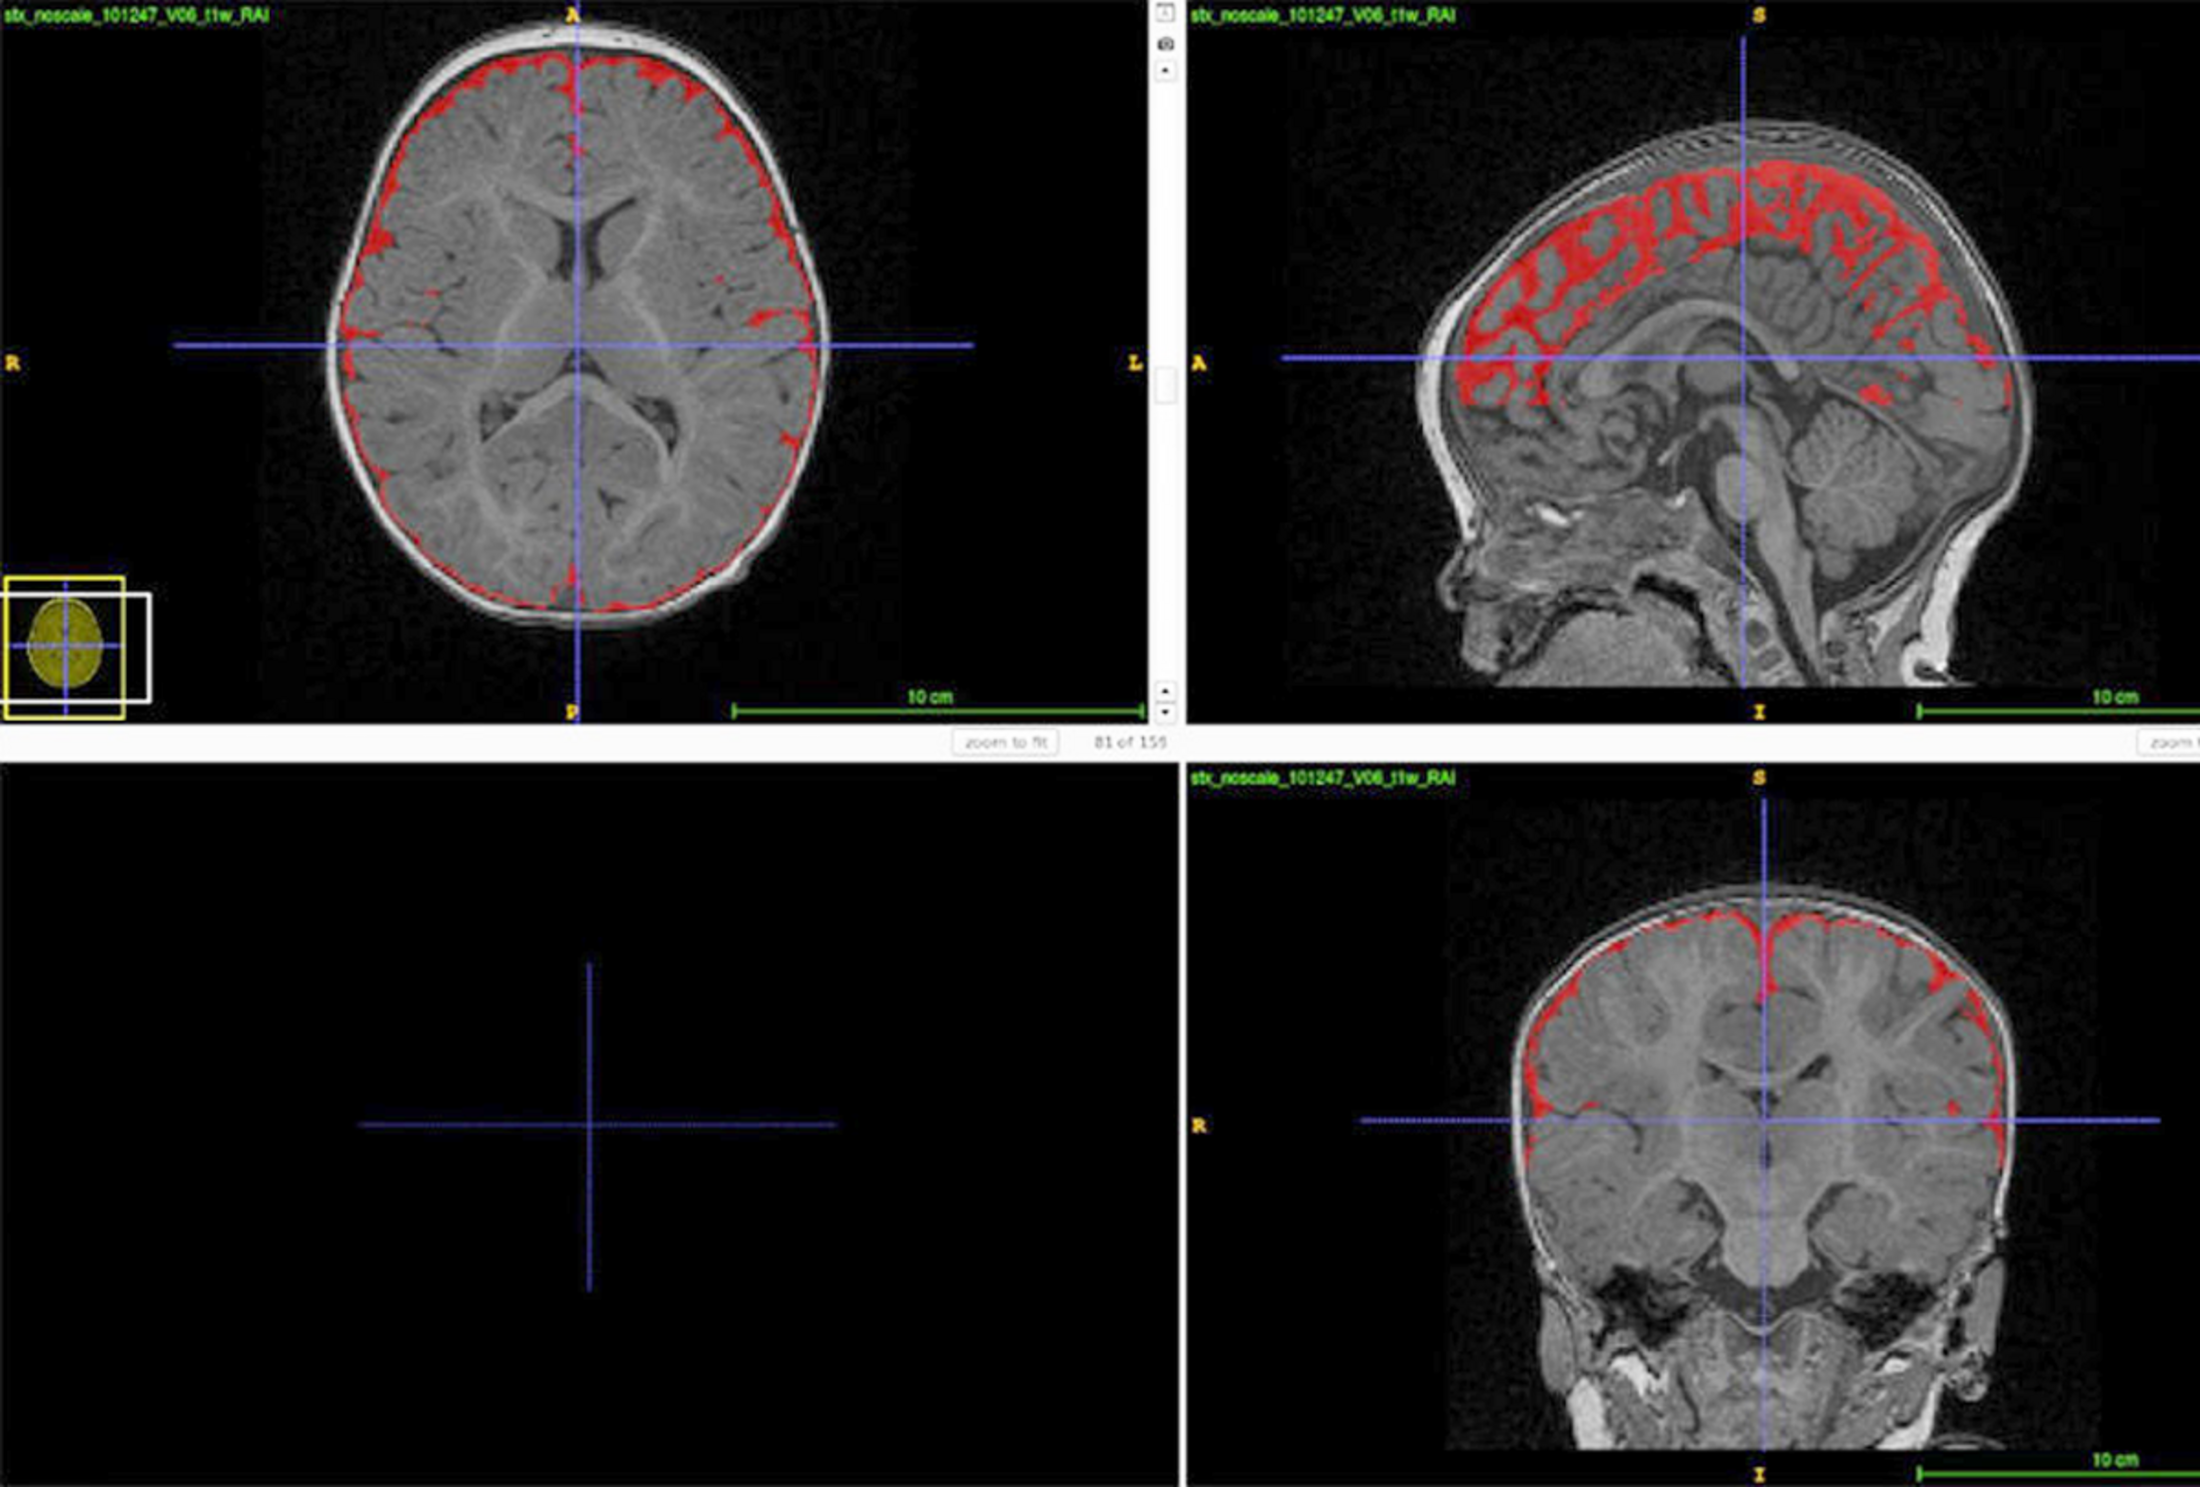

Scanners cérébraux de deux nourrissons présentant des niveaux différents de LCR.

Illustration 2

Gonflement du cerveau : Un nourrisson de 6 mois qui a ensuite été diagnostiqué autiste (rangée du bas) présentait un excès de liquide céphalorachidien entourant le cerveau (représenté en blanc) par rapport à un nourrisson au développement normal (rangée du haut).

Même s'il s'agit d'une petite étude, 8 des 10 bébés de la fratrie de Shen qui ont été diagnostiqués autistes par la suite présentaient un reflux important de LCR - avec environ 20 % de liquide en plus en moyenne que 34 enfants neurotypiques et 11 enfants présentant un retard de développement général évalués par IRM à l'âge de 6 à 9 mois. Et plus les enfants autistes avaient de liquide à l'âge de 6 mois, plus ils présentaient de retards moteurs plus tard dans la petite enfance, selon une étude de suivi plus importante menée par Shen en 2017.